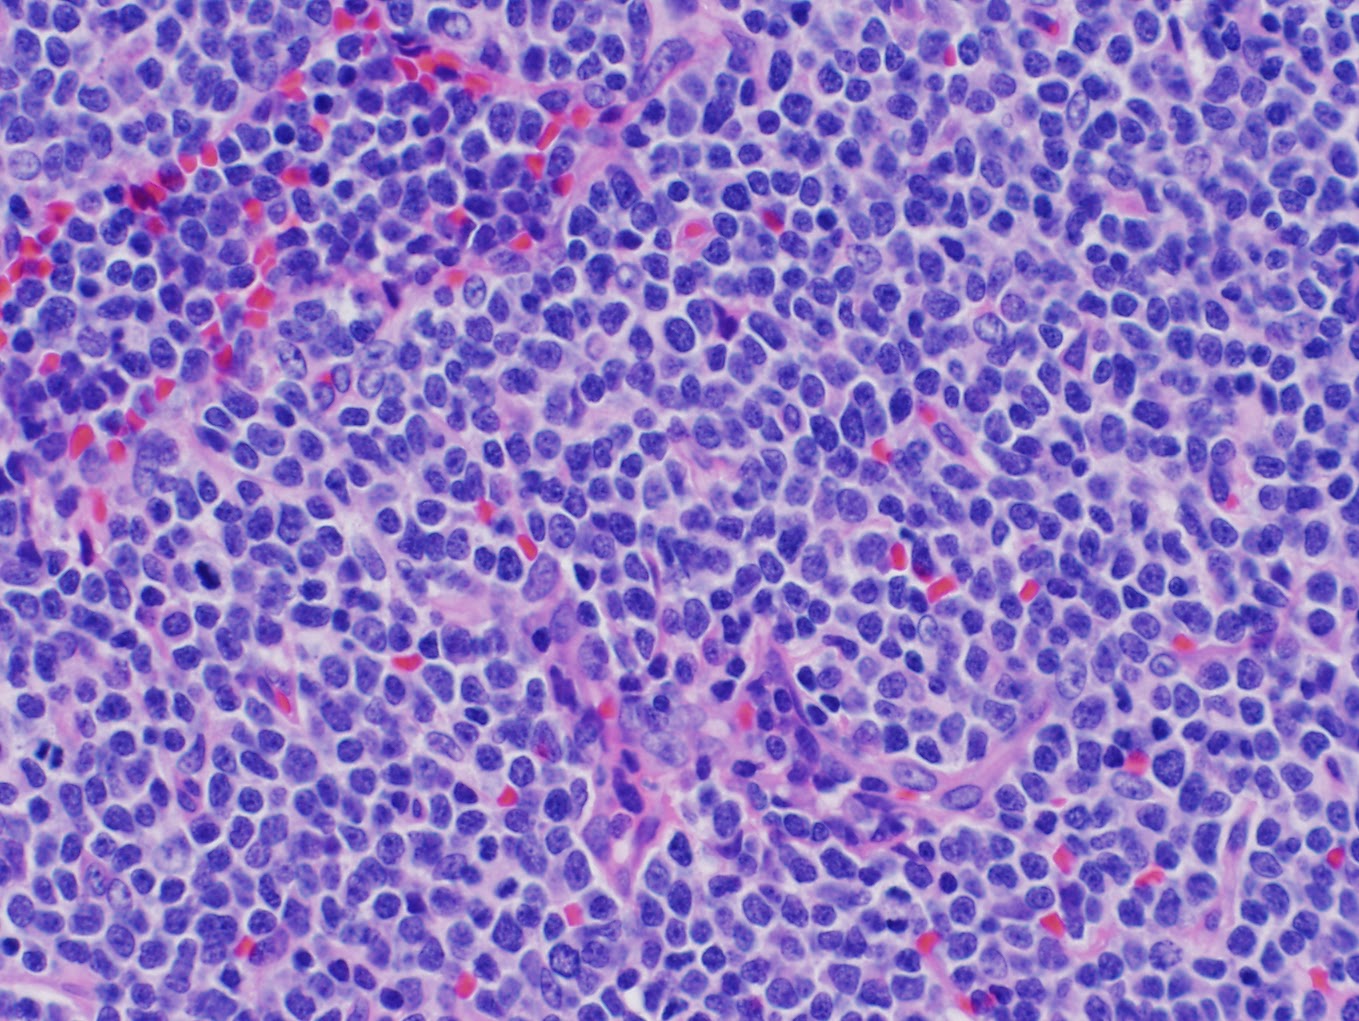

T-CELL LYMPHOBLASTIC LYMPHOMA

One of DIllon's first questions when he came out of surgery was...."Can I see the lymph nodes?" The surgeon told him that it was not possible to see the actual lymph nodes but that he could try to get photos of the slides from the lab where the biopsy analysis was taking place. Dillon was satisfied with that and wanted you all to see what the monster growing in his neck looks like under a microscope.

One of DIllon's first questions when he came out of surgery was...."Can I see the lymph nodes?" The surgeon told him that it was not possible to see the actual lymph nodes but that he could try to get photos of the slides from the lab where the biopsy analysis was taking place. Dillon was satisfied with that and wanted you all to see what the monster growing in his neck looks like under a microscope.